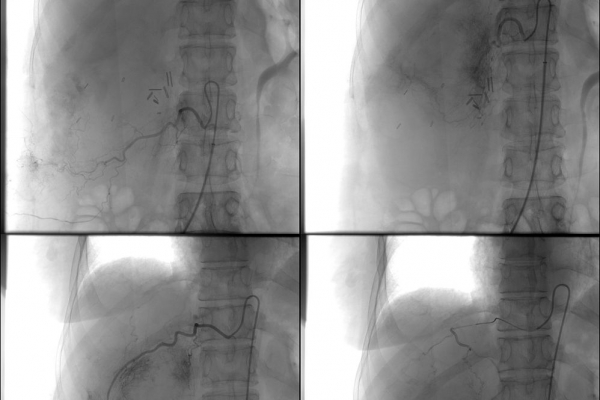

Ο χημειοεμβολισμός είναι μέθοδος τοπικής χημειοθεραπείας για πρωτοπαθή και δευτεροπαθή νεοπλάσματα του ήπατος. Σκοπός του είναι η τοπική έγχυση χημειοθεραπευτικού σε κλάδους της ηπατικής αρτηρίας, ώστε να επιτευχθούν υψηλές συγκεντρώσεις τοπικά στην ηπατική εξεργασία χωρίς να προκαλούνται οι συστηματικές επιπλοκές τοξικότητας του χημειοθεραπευτικού. Επιπλέον προκαλείται τοπική ισχαιμία στην περιοχή του όγκου από τα εμβολικά υλικά-μικροσφαιρίδια εμβολισμού.